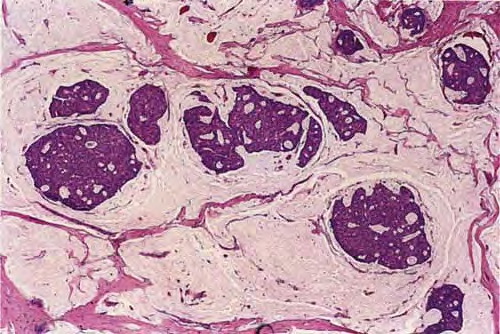

There are solid and cystic aggregations of neoplastic cells within the dermis, often with extension to the subcutis, embedded in large pools of mucin. Mucinous areas are typically separated by fibrous septae.